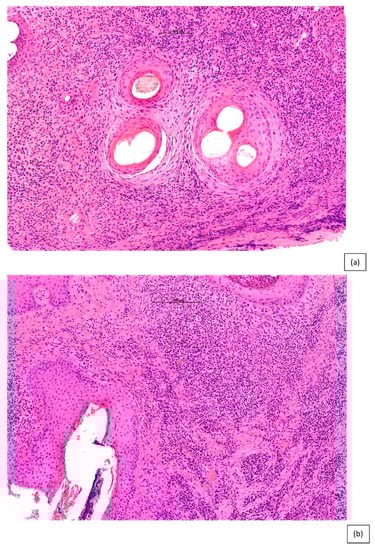

| LPP | CCLE | CCCA | FD | |

|---|---|---|---|---|

| Epidermis and hair follicle epithelium | Sparing of interfollicular epidermis | Interfollicular epidermal changes (follicular plugging, vacuolar alteration and atrophy) | Eccentric atrophy of the follicular epithelium | Flattened and “squamatisation of hair follicle epithelium surrounded by a zone of fibroplasia and inflammation |

| Inflammation | Perifollicular infiltrates (predominately lymphocytic although histiocytes also occur) with sparing of deep vascular plexus and adnexal structures | Superficial and deep lymphocytic infiltrate involving eccrine glands | Variably dense lymphocytic perifollicular inflammation, primarily at the level of the upper isthmus and lower infundibulum | Predominantly neutrophils, with a component of both lymphocytes and plasma cells at varying depths |

| Mucin | Perifollicular | Interfollicular dermal mucin deposition | Perifollicular | Perifollicular |

| DIF | Non- specific globular IgM in Civatte bodies | Linear deposition of IgG, IgM, and C3 at the dermal–epidermal junction and follicular epithelial dermal junction | Negative | Negative |

| Elastic tissue staining | Loss of elastic tissue and the elastic sheath in a superficial wedge-shaped scar | Broad scar throughout the dermis and destruction of the elastic sheath surrounding the fibrous tracts | Hyalinization of the dermis with increased and thickened elastic fibres. Broad fibrous tracts with preserved elastic sheath | Superficial wedge-shaped scar with late diffuse dermal scar/fibrosis |

| Distinguishing features | Peri-follicular infundibular lichenoid (band-like) inflammation and apoptotic bodies | Vacuolar interface change Dermal mucin Thickened basement membrane | PDRIS found in early disease and normal appearing scalp | Polytrichia and hair shaft granulomas as a predominant feature |